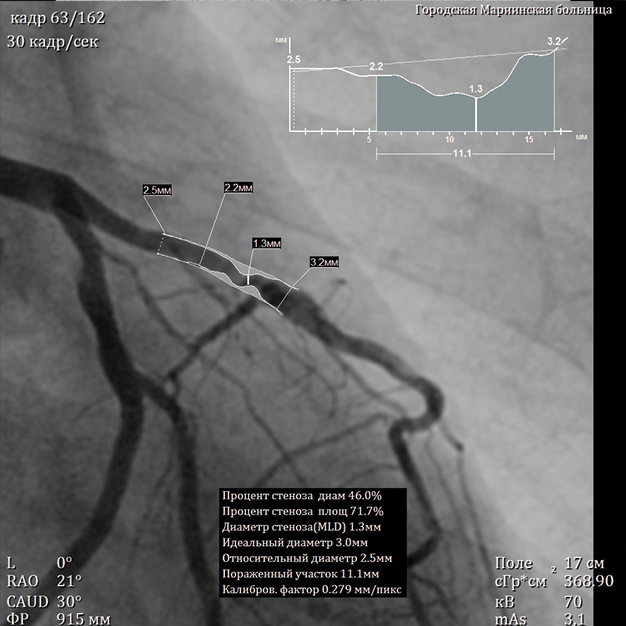

A special value of the angiography system consists in high information content of the obtained image. A unique imaging system based on a flat panel detector with spatial resolution of 50 μm, which is superior to foreign analogs regarding its specifications, ensures high diagnostic imaging quality. The examinations allow not only to obtain information about the functional state of the vessels and reveal the signs of disorders but also help determine the accurate localization and seriousness of the revealed abnormality using special calculation packages.

In addition to the set of standard image processing functions, as well as the vessel and cardiac function parameters calculation packages, the system software includes specialized packages, which are necessary for the effective work of endovascular surgeons:

• Digital subtraction angiography (DSA) with choice of subtraction level (Landmark)